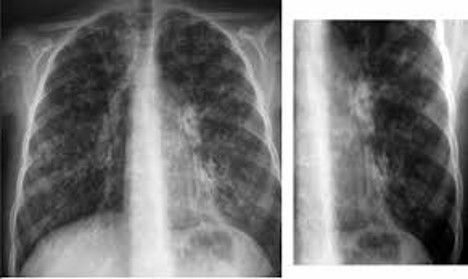

La cirugía de revascularización coronaria (CABG) se asocia a una reducción de la fuerza de los músculos respiratorios y como

El objetivo de esta investigación fue evaluar la efectividad del entrenamiento de músculos respiratorios antes de una cirugía de bypass